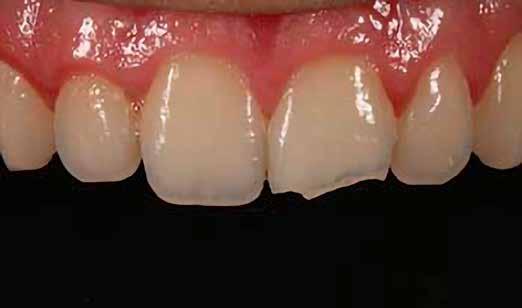

Egy 30 éves, negatív kórtörténettel rendelkező beteg azzal a kéréssel fordult hozzánk, hogy cseréljük ki az UR1 traumája után, 10 évvel korábban készült korábbi kompozit-helyreállítást.

A klinikai vizsgálat során az UR1 reagál a viabilitási tesztre, és az ugyanazon a napon készült röntgenfelvételen nem mutat periapikális elváltozásokat (1. ábra).

Az UR1 elszíneződött, és palatálisabb helyzetben van, mint az ellenoldali központi UL1 (2. ábra)

Az esztétikai elemzés a gingivális zenit aszimmetriáját mutatja az UR1 és az UL1 között. Parodontális szonda segítségével, plexusérzéstelenítés után, az IA

típusú funkcionális hám megváltozott passzív erupcióját igazoljuk Coslet és mtsai. osztályozása szerint (3. ábra)

A lehető legkonzervatívabb helyreállító kezelés elvégzése érdekében a páciensnél, figyelembe véve a megtartott fogelem korát és vitalitását, a tervezés és a diagnosztikai felviaszolás után a közvetlen kompozit-helyreállítás elvégzése mellett döntünk.